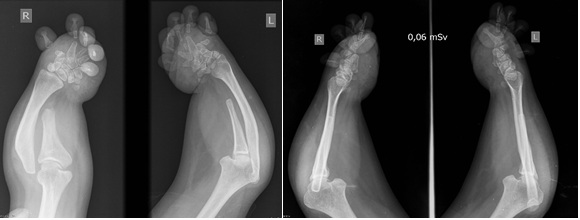

Síndrome de Grebe. Reporte de un caso. [Grebe syndrome. Case report.]